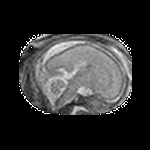

Exp. 3: Adult thorax data: To show the versatility of our approach we also apply it to adult thorax scans. For this experiment no organ specific training is performed but the whole volume is used. We evaluate reconstruction performance similar to Exp. 1 and Ti^^subscript𝑇𝑖\hat{T_{i}} prediction performance when ΩΩ\Omega is projected on an external plane, comparable to X-Ray examination using C-Arms. The latter provides insights about our method’s performance when applied to interventional settings in contrast to motion compensation problems. 60 healthy adult thorax scans were randomly selected, 51 scans used for ΩtrainsubscriptΩ𝑡𝑟𝑎𝑖𝑛\Omega_{train} and nine scans used for ΩvalidationsubscriptΩ𝑣𝑎𝑙𝑖𝑑𝑎𝑡𝑖𝑜𝑛\Omega_{validation}. Each scan is intensity normalised and resampled in a volume of 200×200×200200200200200\times 200\times 200 with spacing 1mm×1mm×1mm1𝑚𝑚1𝑚𝑚1𝑚𝑚1mm\times 1mm\times 1mm. Using the Fibonacci sampling method, 25 sampling plane of size 200×200200200200\times 200, evenly spaced between -50 and +50, were rotated over 500 normals. Training took approximately 20 hours for 60 epochs. Fig. 4c shows an example reconstruction result gaining 28dB PSNR with additional SVR. Ti^^subscript𝑇𝑖\hat{T_{i}} prediction takes approx. 20 ms/slice for this data.

Figure 4: (a): Comparison of a single slice from raw low-dose thorax CT data; (b): reconstruction based on SVRNet Ti^^subscript𝑇𝑖\hat{T_{i}} regression; (c): SVR initialized with SVRNet transformations after four iterations of SVR; (d): PSNR of (b) and (c) compared to (a). (e): shows a projection of an unseen pathological test CT volume as DRR and (e) shows a DRR at the location predicted by our method when presented with the image data in (e).